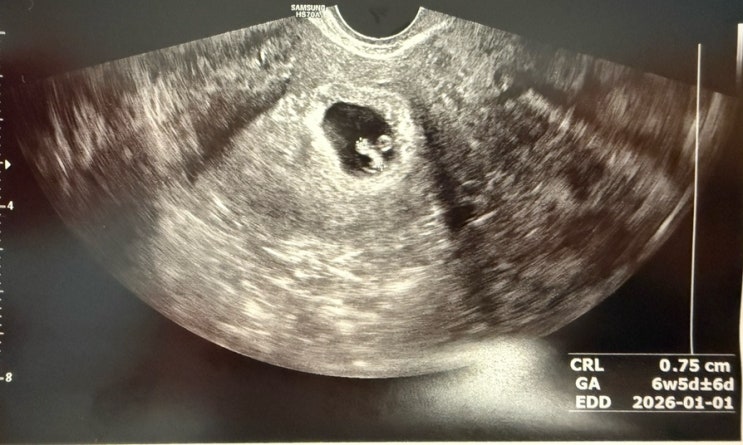

6주-7주 계류유산ㅠ 아기심장소리, 심박수 불안 결국 아기심정지…

피검 수치도 잘 나왔고 아기집 난황 심소 다 잘 보고 잘 들었지만 나는 왠지 계속 불안했다 ㅠㅠ 태몽도 없...

임신초기 6주~7주 기록 아기심소 & 심박수 … 여전히 불안불안

임신 5주 아기집과 난황을 보고 왔지만 그래도 뭐 엄마들에 걱정과 불안은 계속된다 !! 일주일을 무슨 정신...

83년생 난임 시험관성공 아기집 보고왔어요!!

오늘 전주 @@ 산부인과에 방문해 아기집을 보고 왔다~ 이번 차수에 좀 달랐던 점?? 병원을 이전하고 두번만...